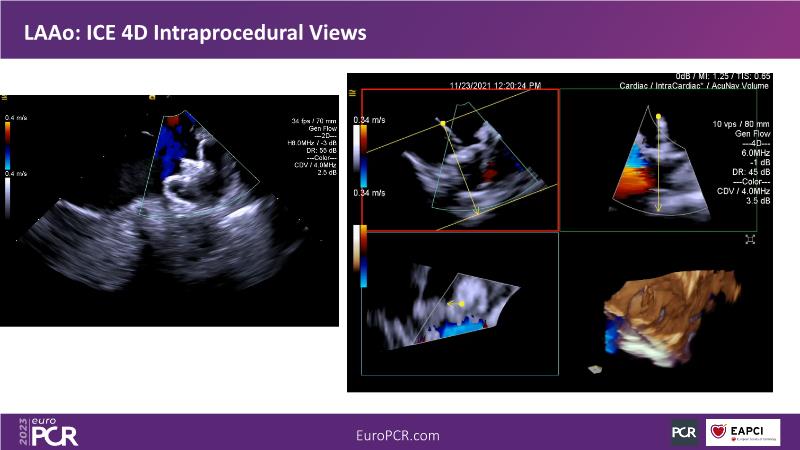

Use of 4D ICE in tricuspid and mitral valve interventions

Watch this session to know the challenges of TV imaging, to get an overview on 4D ICE technology, and to study both a transcatheter tricuspid valve procedure and a transcatheter mitral valve procedure through different case presentations, that will then be discussed.

- To get familiar with the 4D ICE technology and how it can support the imaging and guidance in complex structural heart disease interventions

- To understand the use of 4D ICE and benefits in tricuspid and mitral valve interventions